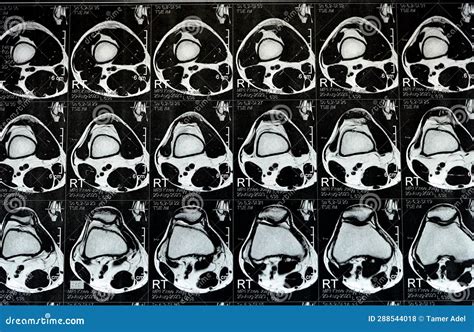

• Positioning: You will lie on a table that slides into the MRI machine. The knee to be scanned will be positioned in a coil to enhance image quality.

Interpreting a Knee Normal MRI involves looking at various structures within the knee to ensure they appear healthy. Key components to examine include:

• axial view of knee mri

• knee anatomy mri axial